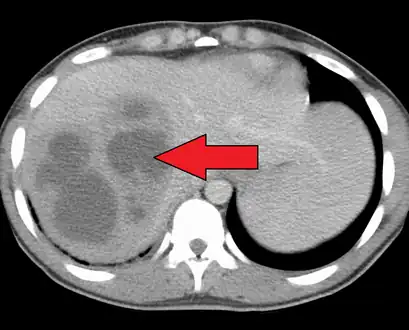

| Liver abscess on axial CT image: a hypodense lesion in the liver with peripherally enhancement. | |

A large pyogenic liver abscess presumed to be the result of appendicitis